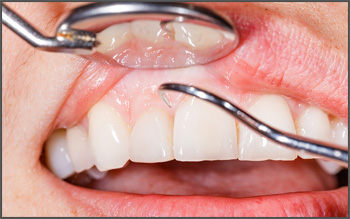

Even with regular and proper brushing and flossing, plaque and tartar will still build up over time. Saliva in our mouths contains calcium and bacteria. Dental plaque is a soft film enveloping teeth which consists of thousands of different types of bacteria embedded in a matrix of proteins, sugars and lipids. Calcified (hardened) dental plaque is known as tartar. Brushing and flossing may remove some plaque but is unable to remove accumulated tartar.

Scaling

Scaling removes plaque and tartar and polishing removes stains and remaining plaque while smoothening and shining teeth so that dental plaque cannot attach easily to tooth surfaces.

Dental scaling and polishing

Dental scaling and polishing is recommended to prevent tooth decay and gum disease, and may be necessary every six months depending on the oral condition of a patient. As infections and diseases can spread from the mouth to the rest of the body, affecting general systemic health, it is important to maintain good oral health and hygiene.

Scaling and Polishing of the teeth, commonly known as tooth cleaning . It is done for the purpose of cleaning of teeth and roots beggings , it involves removing tartar layer and plaque developed on the teeth in the course of time. At Dr. Ehabs Dental Clinic Dubai, it is done by various ways using safe and excellent equipment. We know how important your teeth are for your sound health and your smile.

The Ultrasonic instrument is one of the main instruments used at our dental clinic for scaling process. This equipment removes the tartar layer from the teeth by knocking it out using ultrasonic vibrations. The tool emits a sound with a loud pitch. You may hear this sound little louder than usual because of its direct effect on your ear but you need not to worry about this. If you feel any uneasiness because of the sound, feel free to tell it directly to our dentist who will do his best to make you comfortable enough.

After the cleaning of the teeth, our best dentist in Dubai will use prophy jet to polish any stains on your teeth then a slow speed hand piece is used with a soft rubber cup which keeps on spinning at the end in order to smoothen the enamel using a tooth paste like gel called prophylaxis which comes in various flavours is scooped up in this soft rubber cup to make the teeth smoother. The final thing that the dentist will do is the application of fluoride on your teeth. You will love this step since the fluoride comes in various flavours like pino-colada, watermelon, cherry, strawberry, mind, chocolate etc.

The process of scaling and polishing is extremely safe and is a very pain-free process. In fact, it is recommended to have your teeth cleaned once in every 6 months for optimum oral hygiene.